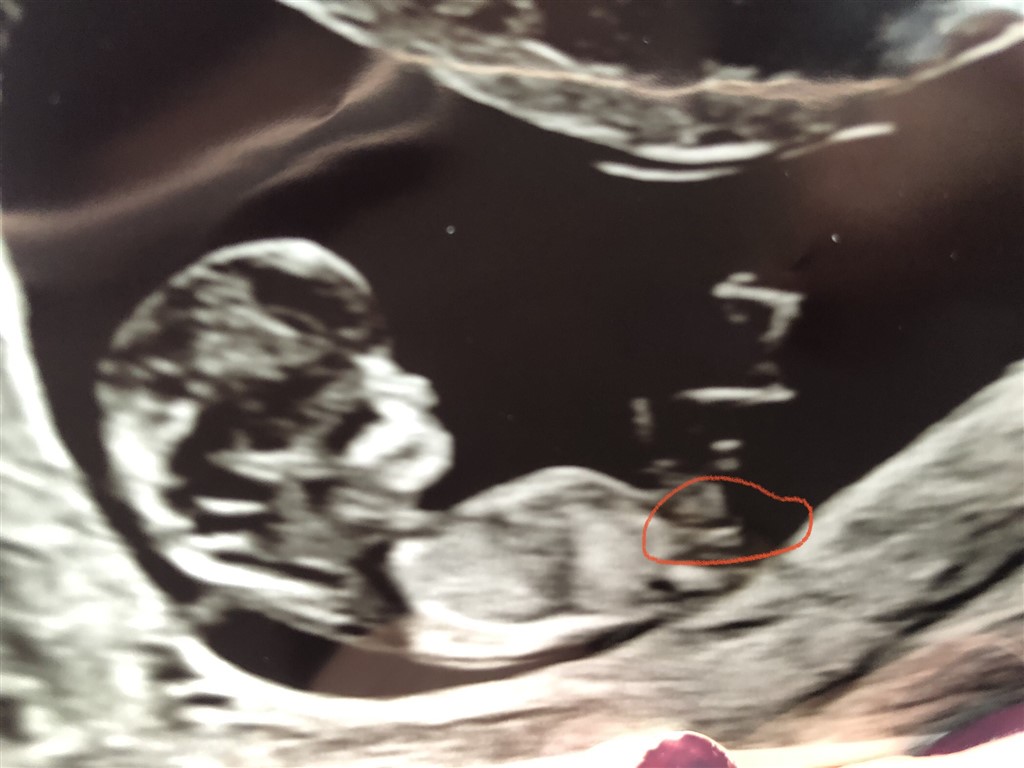

Det er for tidligt at vurdere køn, din babys Nub kan pt gå begge veje, så jeg tør ikke konkludere noget

Min dreng lignede en pige 13+1, hvor alle gættede pige og ingen på dreng - men til kønsscanning var nubben helt rejst, så derfor tør jeg ikke stole på noget så tidligt, hvis jeg var dig